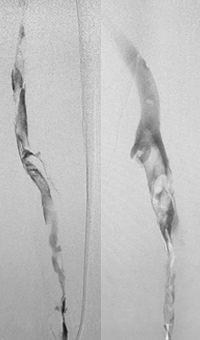

Venous thrombosis extending from popliteal to external iliac vein

Extensive DVT of the right common femoral and external iliac was treated with the 8 F AngioJet™ ZelanteDVT™ catheter.

Patient history

73 year old with 1-week old right leg swelling and pain.  Started on anticoagulation and discharged.

Consult confirmed extensive DVT from popliteal extending into external iliac vein.

Procedural steps

• Power Pulse ( tPA 10 mg in 50 cc)

• Patient put on 2-hour lytic catheter drip in holding area

• Thrombectomy performed with 8F ZelanteDVT catheter

• Directional ability of ZelanteDVT allowed targeting of residual thrombus in Popliteal and Superficial Femoral Vein Post Venography shows complete resolution of thrombus

xray of occlusive thrombus extending into the iliac vein.

Occlusive thrombus extending into the iliac vein

xray of femoral vein pre-treatment.

Femoral vein pre-treatment

xray image of Iliac vein post-ZelanteDVT.

Iliac vein post-ZelanteDVT

xray image of liac vein post-PTA & stent.

Iliac vein post-PTA & stent

Femoral vein post-ZelanteDVT.

Femoral vein post-ZelanteDVT

Images courtesy of Jeffrey Y. Wang, MD FACS, Vascular Surgeon; Horizon Vascular Specialist, Maryland.  November, 2015